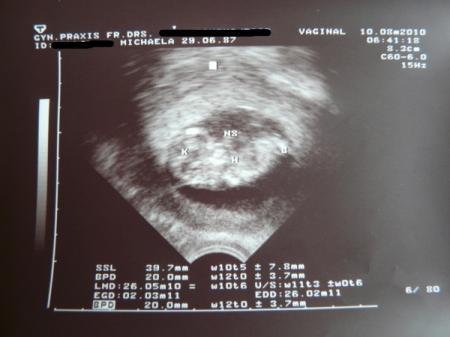

Dann ging es zur Frauenärztin rein und es wurde natürlich auch wieder Ultraschall gemacht. Ich hab jetzt 30 € bezahlt, damit jedes Mal Ultraschall gemacht wird. Ursprünglich hatte ich zwar gedacht, dass mir Ultraschall nicht soo wichtig ist, aber ich merke doch, dass es mir einfach gut tut, regelmäßig zu sehen, dass mit dem Baby alles in Ordnung ist. Ist einfach schön

Mit unserem Baby ist alles bestens, es ist 4 cm groß

das Herz hat schön geschlagen, sonst hat es sich nicht großartig bewegt, es hat wohl geschlafen ;)

Das Ultraschallbild, was ich bekommen habe, lade ich euch gleich noch hoch

Meine Ärztin hat noch drauf geschrieben, was was ist, obwohl ich das auch so erkannt hätte ;-) K ist der Kopf, H das Herz, B ein Bein und NS ist die Nabelschnur.